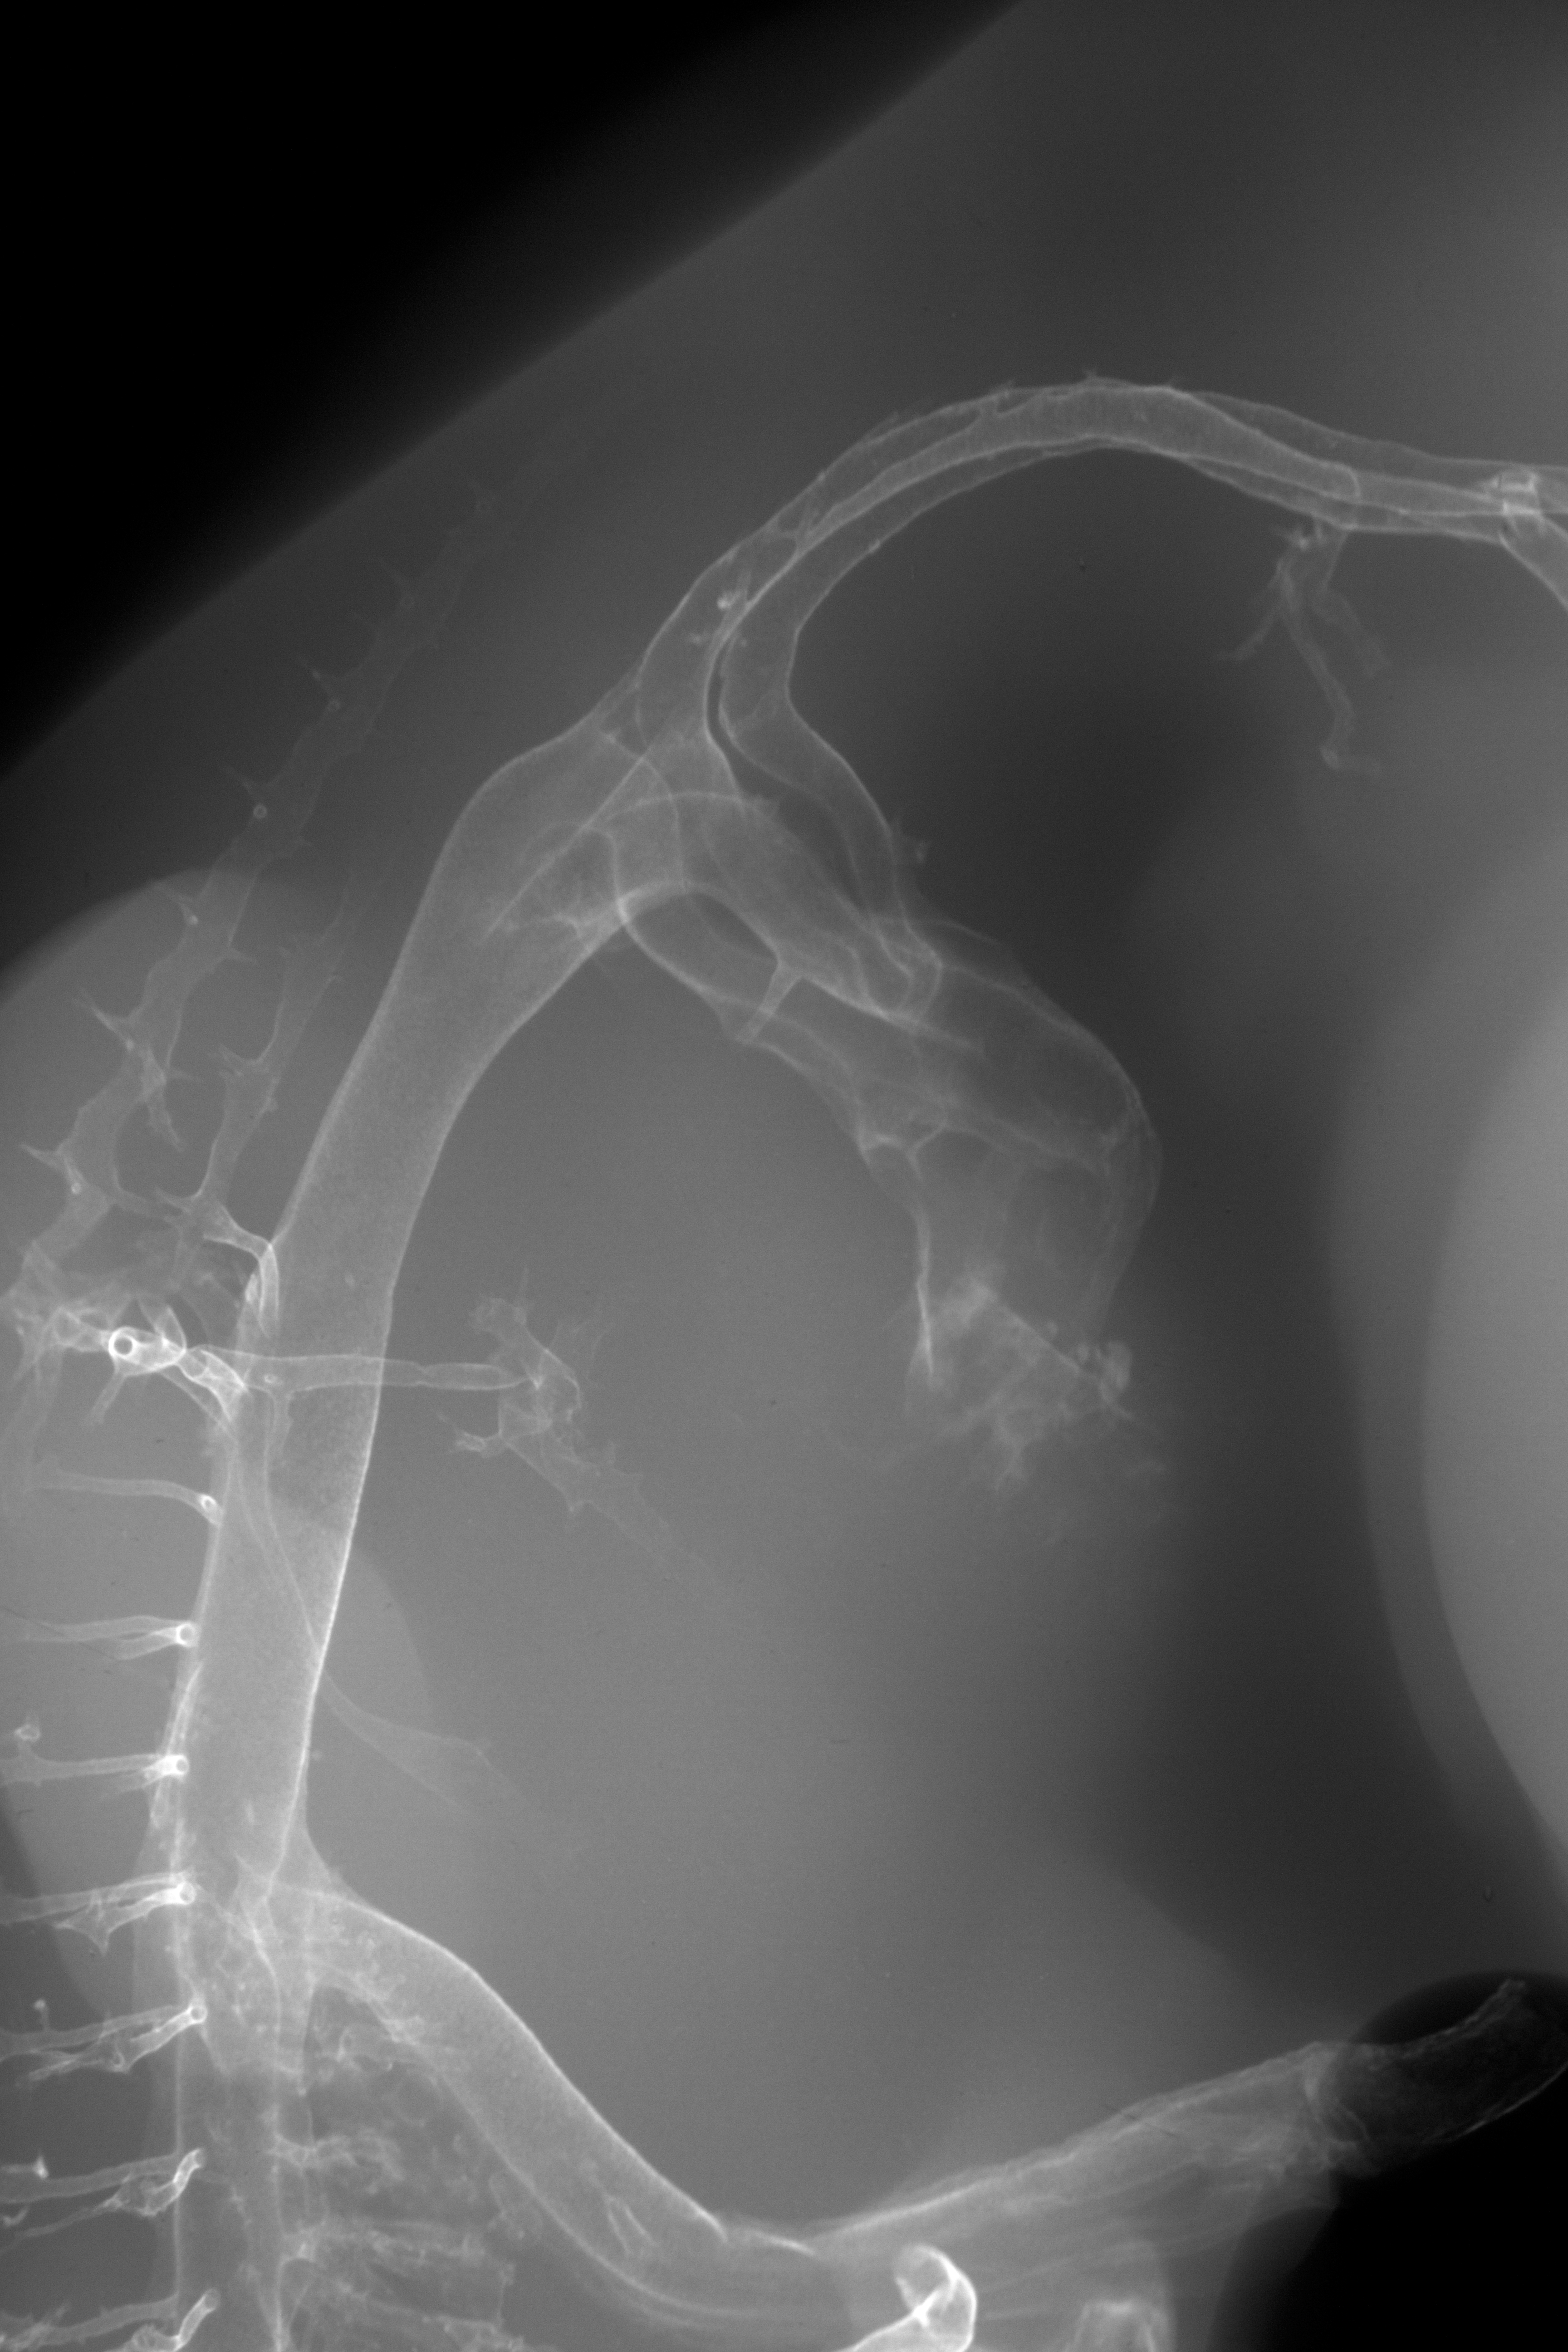

Chick Embryo Microangiography

Hamburger-Hamilton (HH) Stage 28 (approx. 5.5 - 6 days)

X-Ray Micrographs